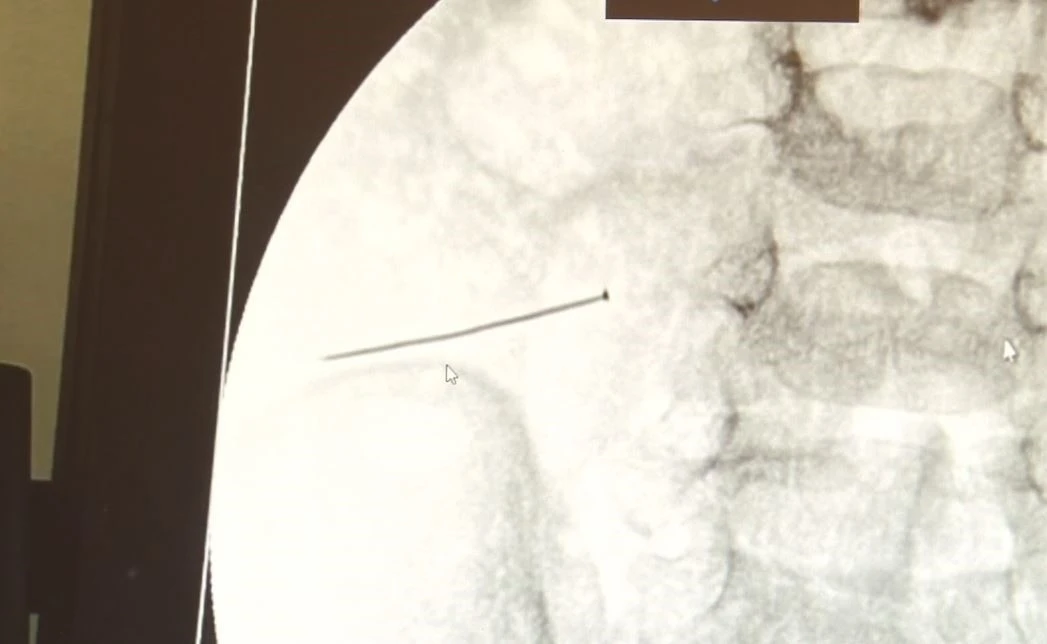

İstanbul’da 2 yaşındaki çocuk iddiaya göre 3 santimlik iğne yuttu, bağırsağı delen iğne başarılı operasyonla çıkarıldı. Ameliyatı gerçekleştiren Çocuk Cerrahisi Uzmanı Doç. Dr. Sefa Sağ, "Yaklaşık 3 santim boyunda bir toplu iğnenin ince bağırsağı deldiğini ve içeriğin de karın içerisine dolduğunu gördük. Ameliyatı başarılı bir şekilde tamamladık, yaklaşık 1 saat süren bir ameliyattı. Çok ciddi bir karın ağrısı, kusma söz konusuydu, ameliyatını yapmasaydık Allah göstermesin çocuğun ölümüyle sonuçlanabilecek bir hadiseydi, çok dikkatli olunmalı" dedi.

İstanbul’da 2 yaşındaki çocuk iddiaya göre toplu iğne yuttu sonrasında adeta karın ağrısıyla yerinde duramaz hale geldi. Babaanne, küçük çocuğun şikayetleri üzerine Şehit Prof. Dr. İlhan Varank Sancaktepe Eğitim ve Araştırma Hastanesi’ne götürdü. Burada yapılan tetkiklerde 2 yaşındaki çocuğun ince bağırsağında yaklaşık 3 santimlik toplu iğne olduğu ve bağırsağı deldiği belirlendi. Görüntülemeler sonrası 30 Ekim akşamı Çocuk Cerrahisi Kliniği Eğitim ve İdari Sorumlusu Doç. Dr. Sefa Sağ ve ekibi hemen ameliyata girdi. Başarılı operasyonla iğne olduğu noktadan alınırken aile de rahat bir nefes aldı. Doç. Dr. Sağ ise taburcu edilen hastasının durumuna ilişkin bilgi verirken yabancı cisim yutmalarına karşı ailelere önemli uyarılarda bulundu. "Yaklaşık 3 santim toplu iğnenin ince bağırsağı deldiğini, içeriğin karın içerisine dolduğunu gördük"

Çocuklarda yabancı cisim yutulmasına yönelik konuşan ve hastasına ilişkin bilgi veren Doç. Dr. Sefa Sağ, "Soluk borusuna kaçması durumunda çocuğun Allah göstermesin ölümüyle veya ömür boyunca yatağa bağımlı kalmasıyla neticelenebilecek sonuçlar doğurabiliyor. Yutulması durumunda da gastrointestinal sistemin herhangi bir yerine takılmadığı müddetçe ekseriyâ yabancı cisimlerin dışarıya çıkmasını bekliyoruz. Yabancı cisim yutulmasını 2 grupta inceleyebiliriz. Sıvı ve katı cisimler olarak sıvı; evde kullanılan kimyasal temizlik malzemelerinin yutulması çok ciddi problemler oluşturabilmekte. Ağızda, yemek borusunda ve midede yanıklar meydana getirebilmekte. Uzun dönemde çocukların hayat kalitesini oldukça etkileyen sonuçlar doğurabilmekte. Katı cisimlerden de ekseriyâ kendiliğinden çıkmasını bekleriz ancak böyle delici, kesici aletlerin yutulmasında ise herhangi bir bağırsağın veya gastrointestinal sistemin bir parçasında delinmeler meydana getirebiliyor. Bu çocuğumuzda da aynen böyle bir hadise meydana gelmişti. Sanırım 1 gün önce ailenin yuttuğunu tahmin ettiği bir yabancı cisim; toplu iğne. Ertesi gün bağırsakta delinmeyle sonuçlanmış ve çocukta da ciddi semptomlar meydana getirmişti. Bu şekilde hasta bize başvurdu. Tetkikler sonucunda yabancı cismi tespit ettik, semptomları ve bulgularına göre de çocuğu ameliyata aldık. Yaklaşık 3 santim boyunda bir toplu iğnenin ince bağırsağı deldiğini, ince bağırsaktaki içeriğin de karın içerisine dolduğunu gördük. Ameliyatı başarılı bir şekilde tamamladık, yaklaşık 1 saat süren bir ameliyattı" dedi. "Çocuğun ölümüyle sonuçlanabilecek bir hadiseydi"

Öte yandan, yaklaşık 3 santimlik toplu iğne filme yansıyan görüntüsüyle gözler önüne serildi.